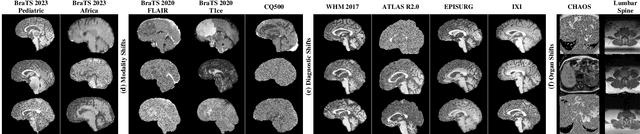

Abstract:Out-of-distribution (OOD) detection is crucial in AI-driven medical imaging to ensure reliability and safety by identifying inputs outside a model's training distribution. Existing methods often require retraining or modifications to pre-trained models, which is impractical for clinical applications. This study introduces a post-hoc normalizing flow-based approach that seamlessly integrates with pre-trained models. By leveraging normalizing flows, it estimates the likelihood of feature vectors extracted from pre-trained models, capturing semantically meaningful representations without relying on pixel-level statistics. The method was evaluated using the MedMNIST benchmark and a newly curated MedOOD dataset simulating clinically relevant distributional shifts. Performance was measured using standard OOD detection metrics (e.g., AUROC, FPR@95, AUPR_IN, AUPR_OUT), with statistical analyses comparing it against ten baseline methods. On MedMNIST, the proposed model achieved an AUROC of 93.80%, outperforming state-of-the-art methods. On MedOOD, it achieved an AUROC of 84.61%, demonstrating superior performance against other methods. Its post-hoc nature ensures compatibility with existing clinical workflows, addressing the limitations of previous approaches. The model and code to build OOD datasets are available at https://github.com/dlotfi/MedOODFlow.